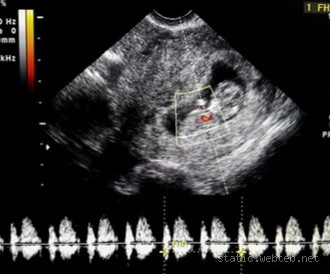

حسنًا، في الشهر الأول من الحمل، الجنين لا يكون قد تطور بما فيه الكفاية ليُسمع نبضه بسهولة. عادةً ما يكون القلب قد بدأ في التكون في الأسبوع الخامس من الحمل، ولكن من الصعب سماع نبضه في هذه المرحلة باستخدام جهاز السونار التقليدي. في الواقع، عند معظم النساء، لا يُسمع النبض إلا في الأسبوع السادس أو السابع من الحمل، وحتى حينها، قد تحتاجين إلى جهاز سونار مخصص أو زيارة الطبيب لاكتشافه.

حسنًا، رغم أنه من غير المعتاد سماع نبض الجنين في الشهر الأول، إلا أن هناك بعض الطرق التي قد تساعد الأطباء في مراقبة تطور الجنين في هذه المرحلة. باستخدام جهاز السونار الداخلي (الموجات فوق الصوتية)، يمكن للطبيب الكشف عن نبض القلب في وقت مبكر من الحمل، لكن هذا عادةً يحدث في الأسبوع الخامس أو السادس.

أعتقد أن هذه النقطة كانت محيرة بالنسبة لي في البداية. كنت أتمنى سماع نبض الجنين في الأسبوع الرابع أو الخامس، ولكن عند إجراء أول فحص بالسونار في الأسبوع السادس، تمكنت من سماع نبض الجنين بوضوح، وكان ذلك شعورًا لا يوصف.

عادةً ما يبدأ نبض الجنين في الشهر الثاني، خصوصًا في الأسبوع السادس من الحمل. على الرغم من أن بعض النساء قد يسمعن نبض الجنين في هذه المرحلة، فإن البعض الآخر قد يحتاج إلى فحص أكثر تخصصًا أو وقتًا أطول لملاحظة النبض بوضوح. والجدير بالذكر أن نبض الجنين في هذه الفترة يكون خفيفًا وسريعًا جدًا، وهو ما يختلف عن نبضات القلب التي نسمعها في مراحل متقدمة من الحمل.

Well، في الشهر الأول من الحمل، من غير المعتاد سماع نبض الجنين، ولكن نبض القلب يبدأ في التكون في الأسبوع الخامس أو السادس من الحمل. في هذه المرحلة، قد يكون من الصعب على الأطباء سماع النبض باستخدام السونار العادي، لكن لا داعي للقلق، فهذا جزء طبيعي من تطور الحمل. إذا كنتِ في هذه المرحلة المبكرة، حافظي على هدوئك وتواصلي مع طبيبك إذا كان لديكِ أي مخاوف. الحمل رحلة مذهلة، وكل شيء يحدث في وقته!